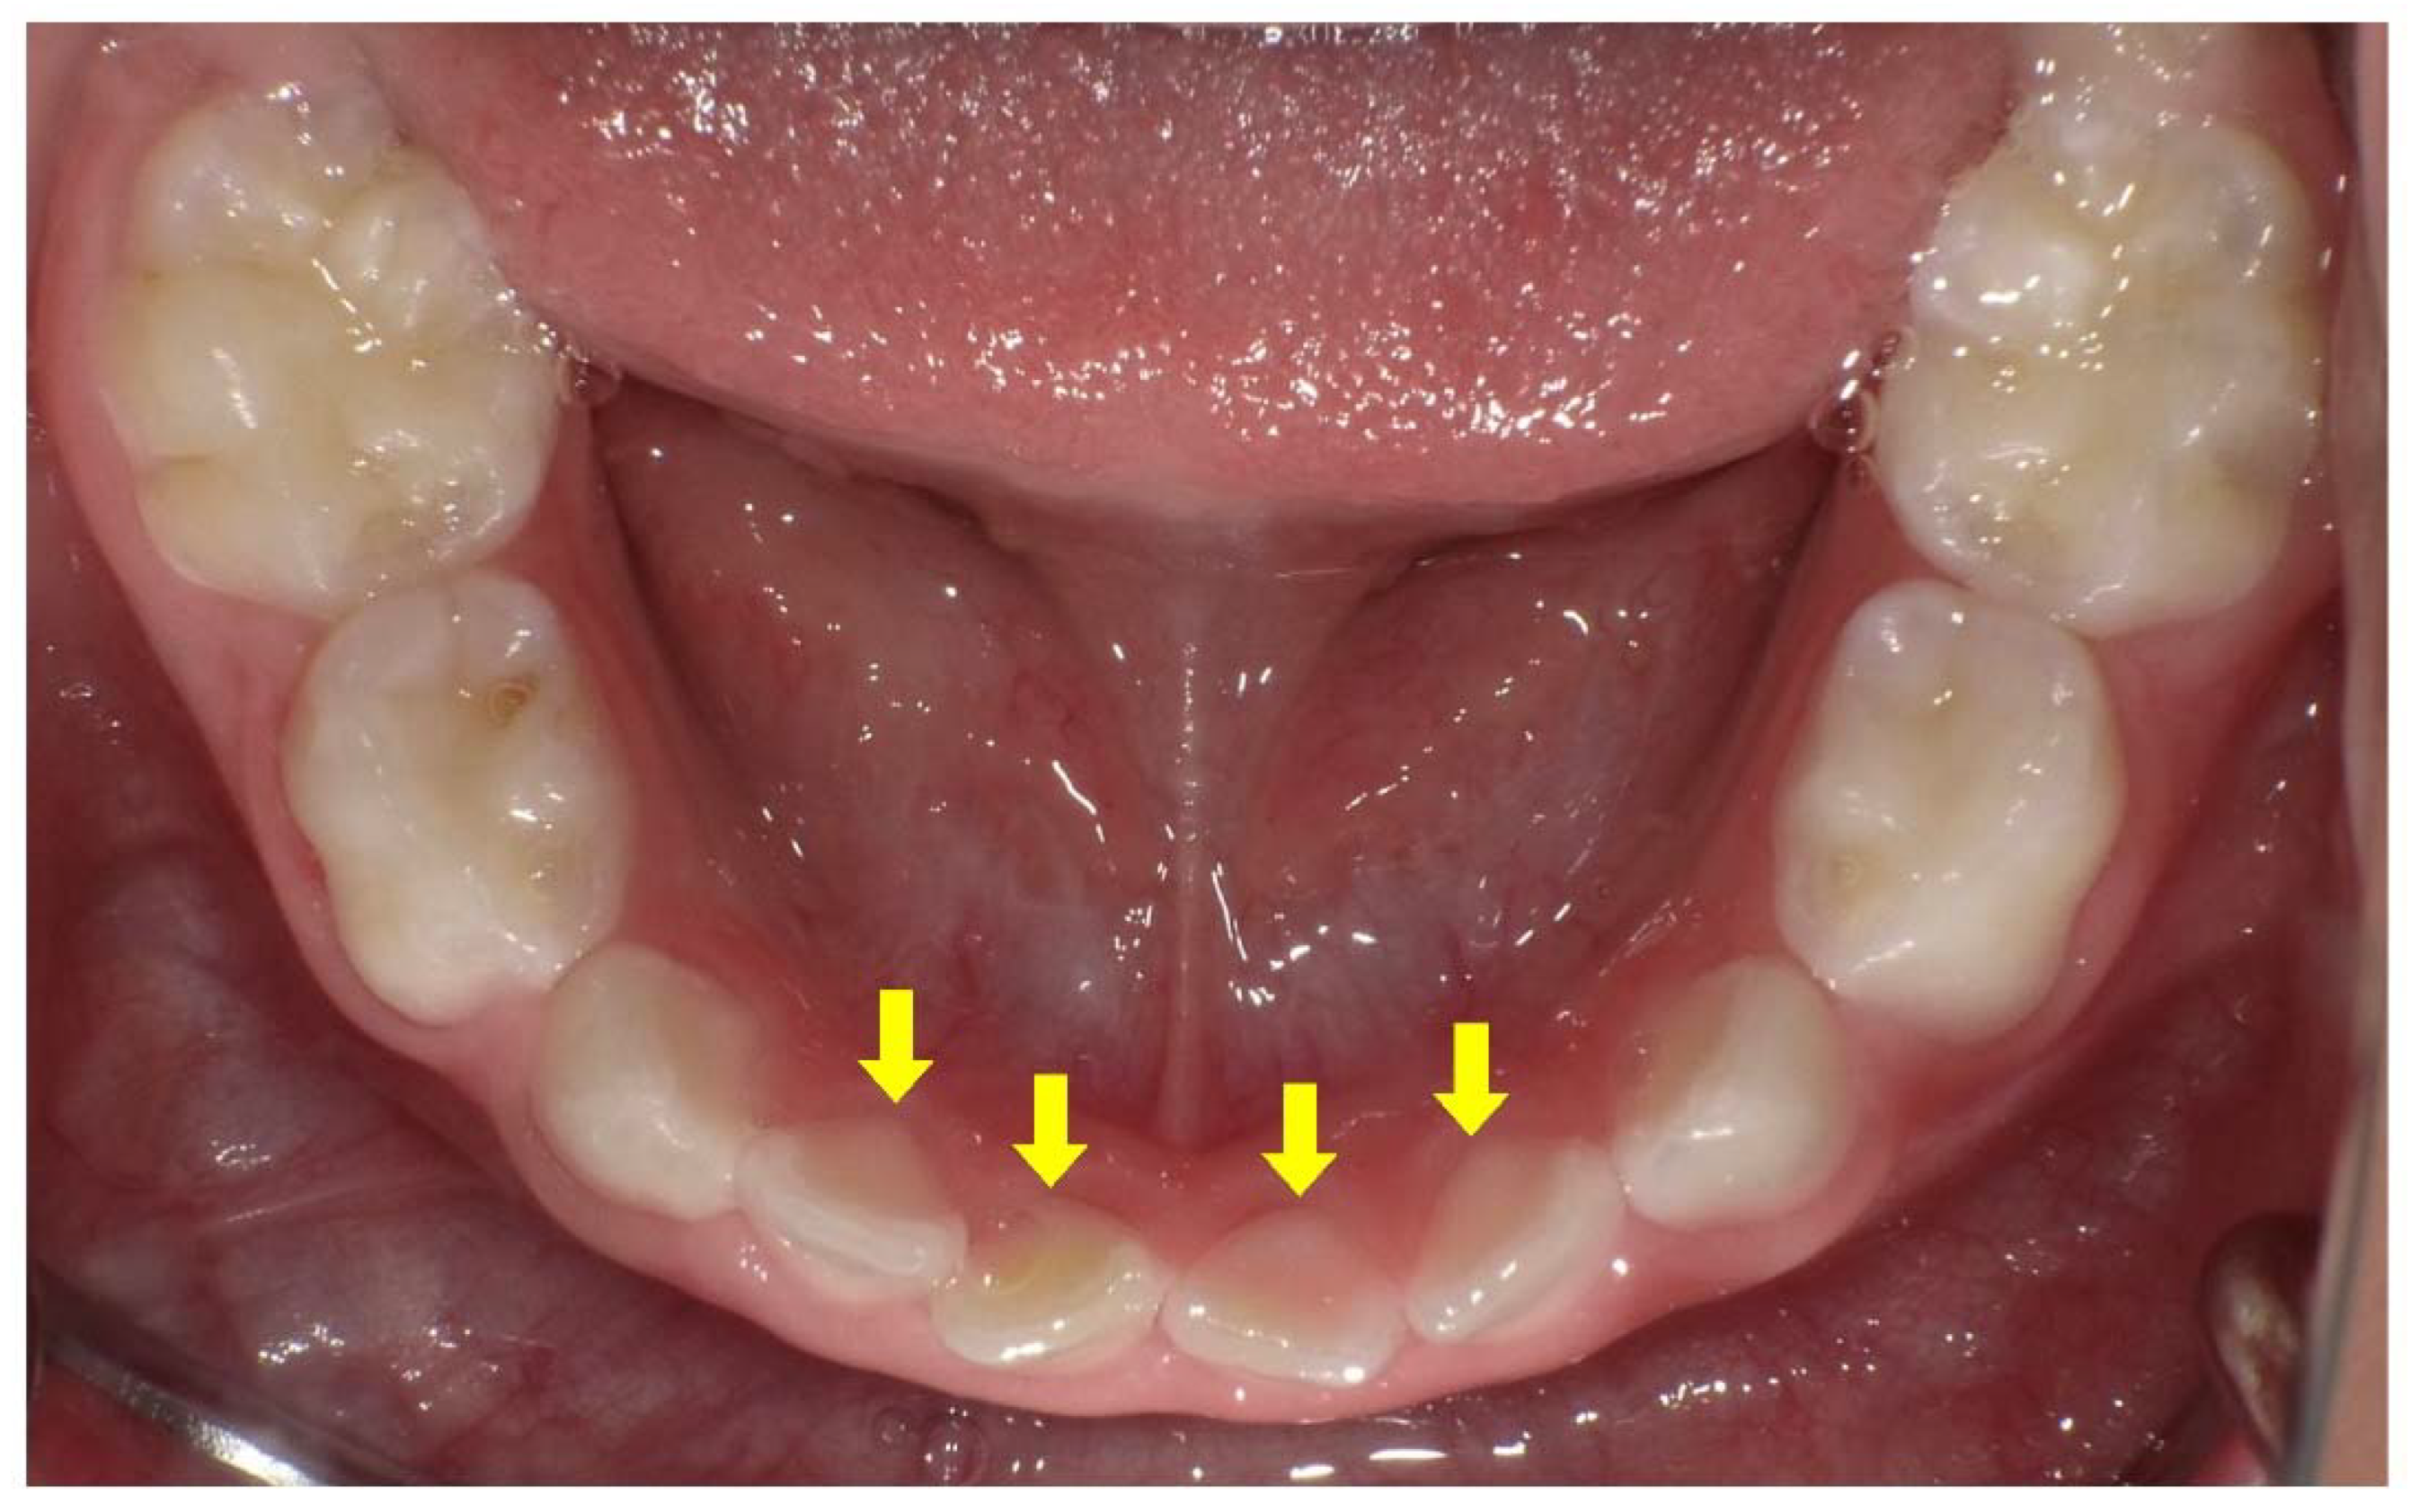

- Okawa, R.; Hamada, M.; Takagi, M.; Matayoshi, S.; Nakano, K. A Case of X-Linked Hypophosphatemic Rickets with Dentin Dysplasia in Mandibular Third Molars. Children 2022, 9, 1304. [Google Scholar] [CrossRef]